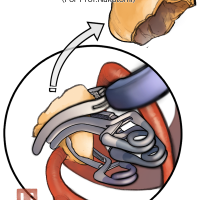

術後イラストシリーズ